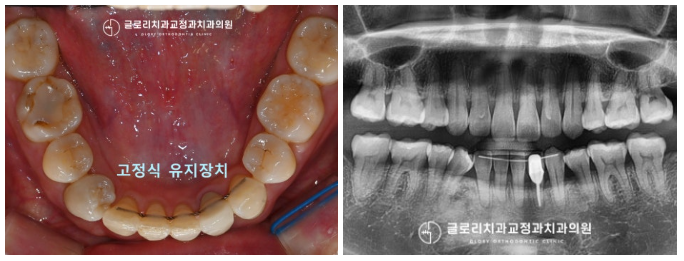

중랑구교정치과 에서는

고정식 유지 장치 부착으로

3개월간의 모든 과정을 마쳤습니다.